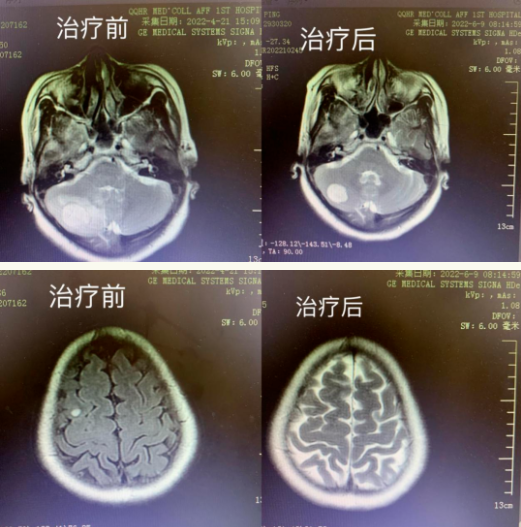

治疗前后对比

我们可以看到,该患者满肺的转移病灶几乎清除殆尽,脑转移病灶缩小明显,大部分已经消失。